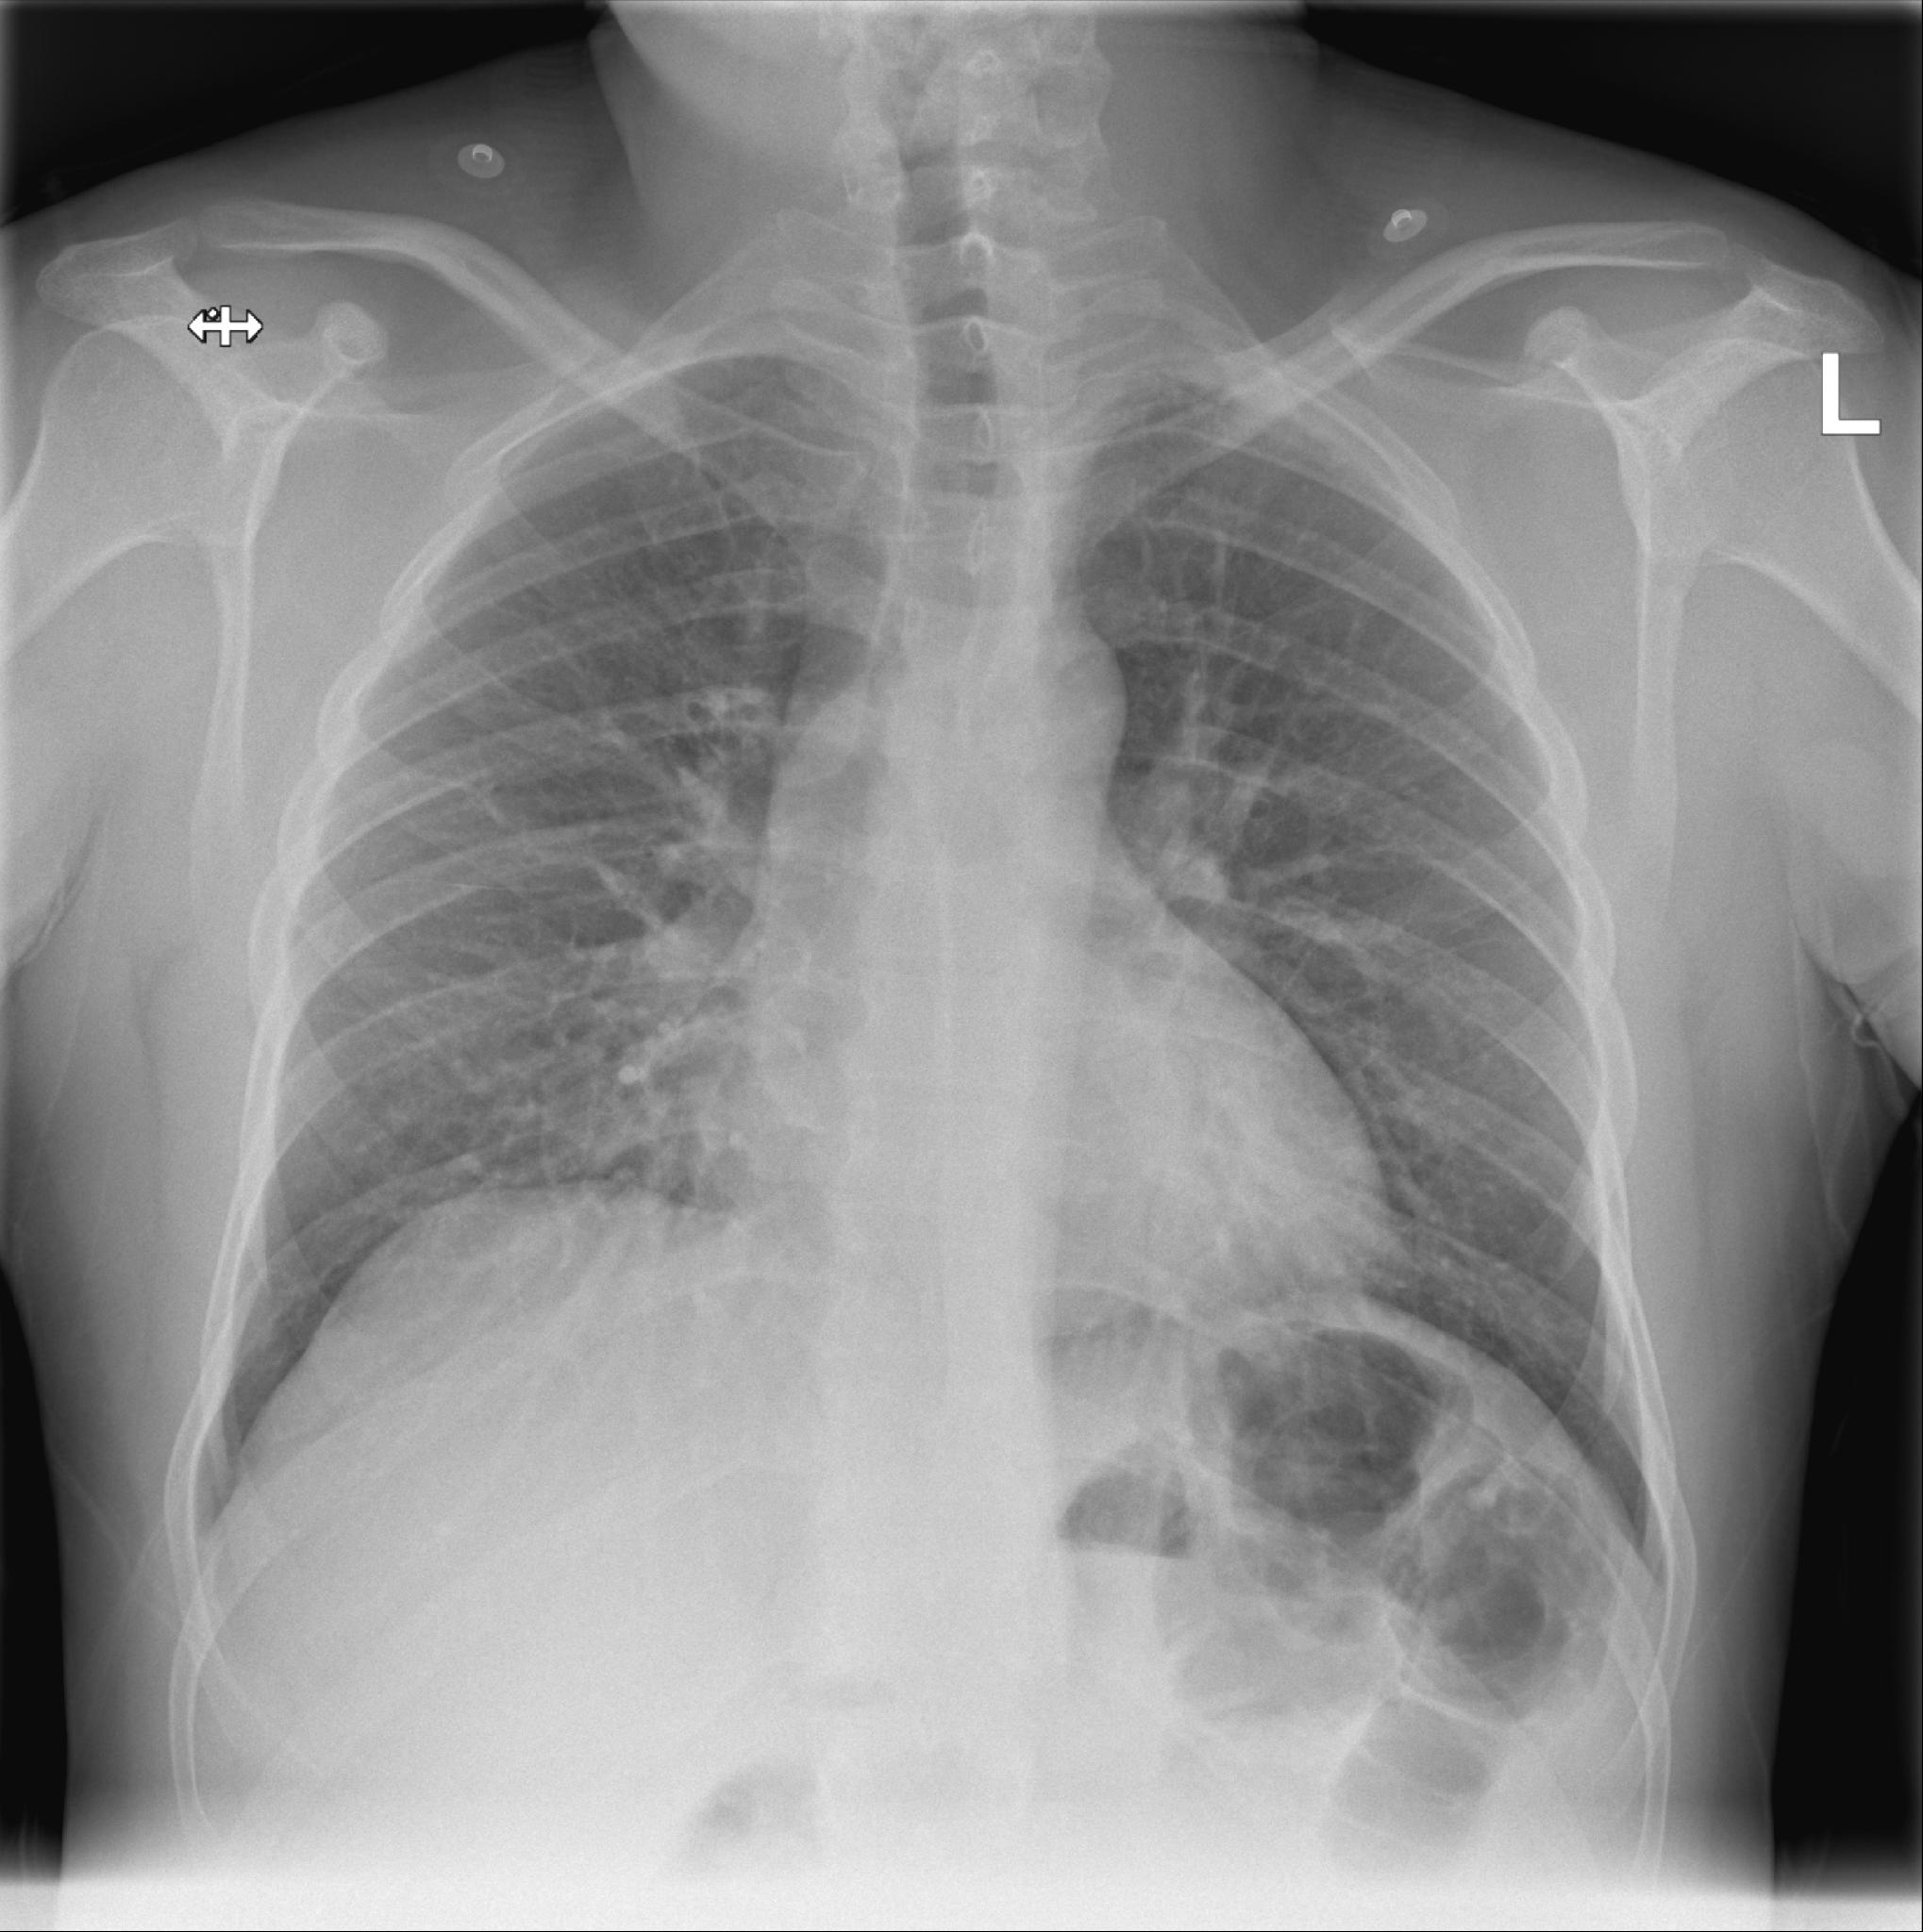

Scherp afgrensbaar diafragmakoepel. Heldere sinus pleura. Slank mediastinum superior. Hili opgebouwd uit bronchovasculaire structuren. Corfiguur binnen de norm. Longvaattekening binnen de norm. Geen circumscripte consolidaties. Echter matig afgrensbaar rechter harthelft. Afgebeeld bovenbuik zonder bijzonderheden. Skelet zonder relevante nevenbevindingen. Conclusie: Geen circumscripte consolidaties. Echter matig afgrensbaar rechter harthelft, beginnende consolidatie middenkwab niet uit te sluiten.

Bert heeft wel gelijk. Voor nu kan ik zeggen dat de foto dus als normaal wordt afgegeven met als enige bijzonderheid dat de rechter zijde van het hart niet scherp is te zien. Daar ligt de middelste van de 3 rechter  longkwabben tegen aan en misschien zit daar een kleine ontsteking. Het kan ook zijn dat er niks aan de hand is. Het mooist  zou zijn als er eerder al eens een foto is gemaakt om te vergelijken. Maar bespreek  het dus met je arts.

Beste Luuk, bedankt voor je snelle reactie. ik heb helaas geen foto die eerder is gemaakt, wel heb ik een foto van de zijkant die de zelfde tijd is gemaakt.